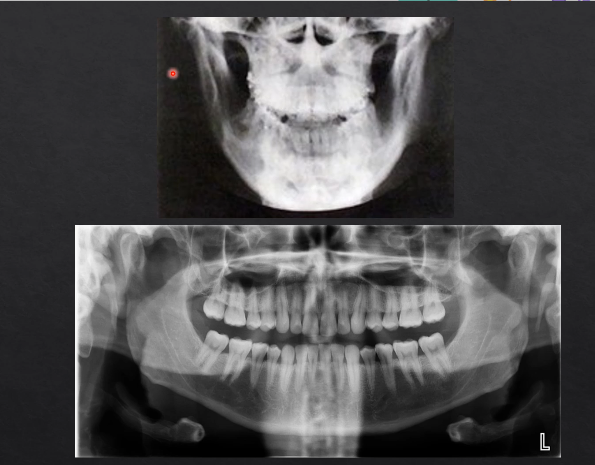

panoramic DPT cont’d

extraoral because the detector is outside of the patient’s mouth

both the source and the detector will rotate round the patient’s head by 180 degrees

taking X rays at different angles around the patient as it moves round the circumference

as the X rays are produced at the detector they are columnated to an envelope shaped beam - see image where the X rays are produced

then they pass through the patient and are collimated again at the detector at an enveloped shaped area

with a single projection taken at one point of rotation - there is an exposed slit of the detector

with each degree of rotation we are only exposing a a letterbox slit of the detector

as we move points of rotation , more and more of the detector gets exposed → at 180 degrees we fully expose the whole length of the detector

each bit of the detector is being exposed but separately - like a printer - or like a panoramic photo → but this creates some geometric distortion

why is it called a dental PANORAMIC TOMOGRAPH

panoramic - small parts/images stitched together to form the full image

tomograph - refers to the part where we’re taking a slice through the patient’s anatomy